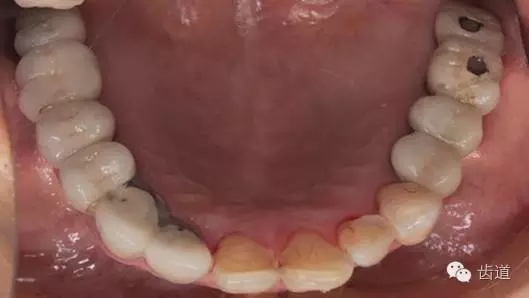

口內(nèi)檢查:

17-12,24-25烤瓷橋修復(fù),邊緣密合可,探-,叩-,松-。

35-38烤瓷橋修復(fù)體,邊緣密合欠佳,探針可探入,探-,叩-,松-。

17,16,26,27,36,37,47缺失。

46,45殘冠,部分白色充填物,繼發(fā)齲壞,探-,叩-,松-。

34遠(yuǎn)中鄰面深齲壞,探+,冷+,叩-,松-。

全口衛(wèi)生情況欠佳,可探及齦上及齦下牙結(jié)石,有牙齦探診出血,有牙齦退縮及牙周附著喪失。

3、下頜牙合面觀